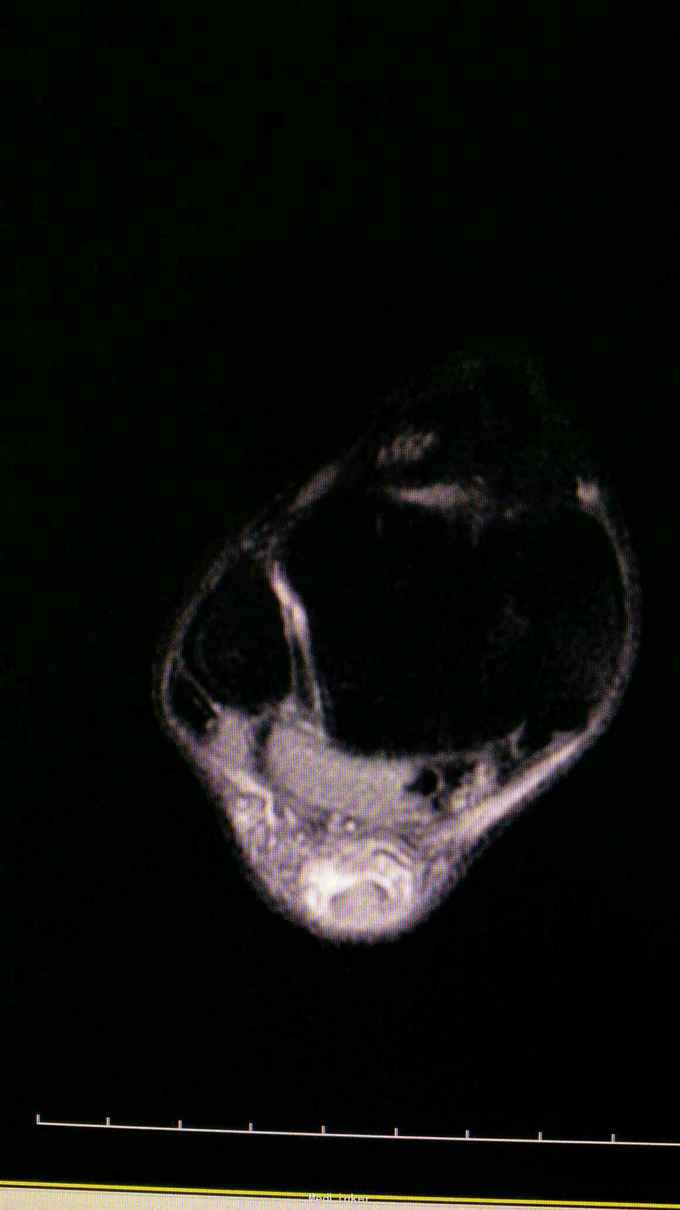

25岁男性,3月前运动受伤导致右跟疼痛,在当地按扭伤处理,现跟部疼痛,无力来诊。

跟腱止点彭大,上方空虚,压痛,提踵试验阳性。

右跟腱陈旧断裂,拟手术重建